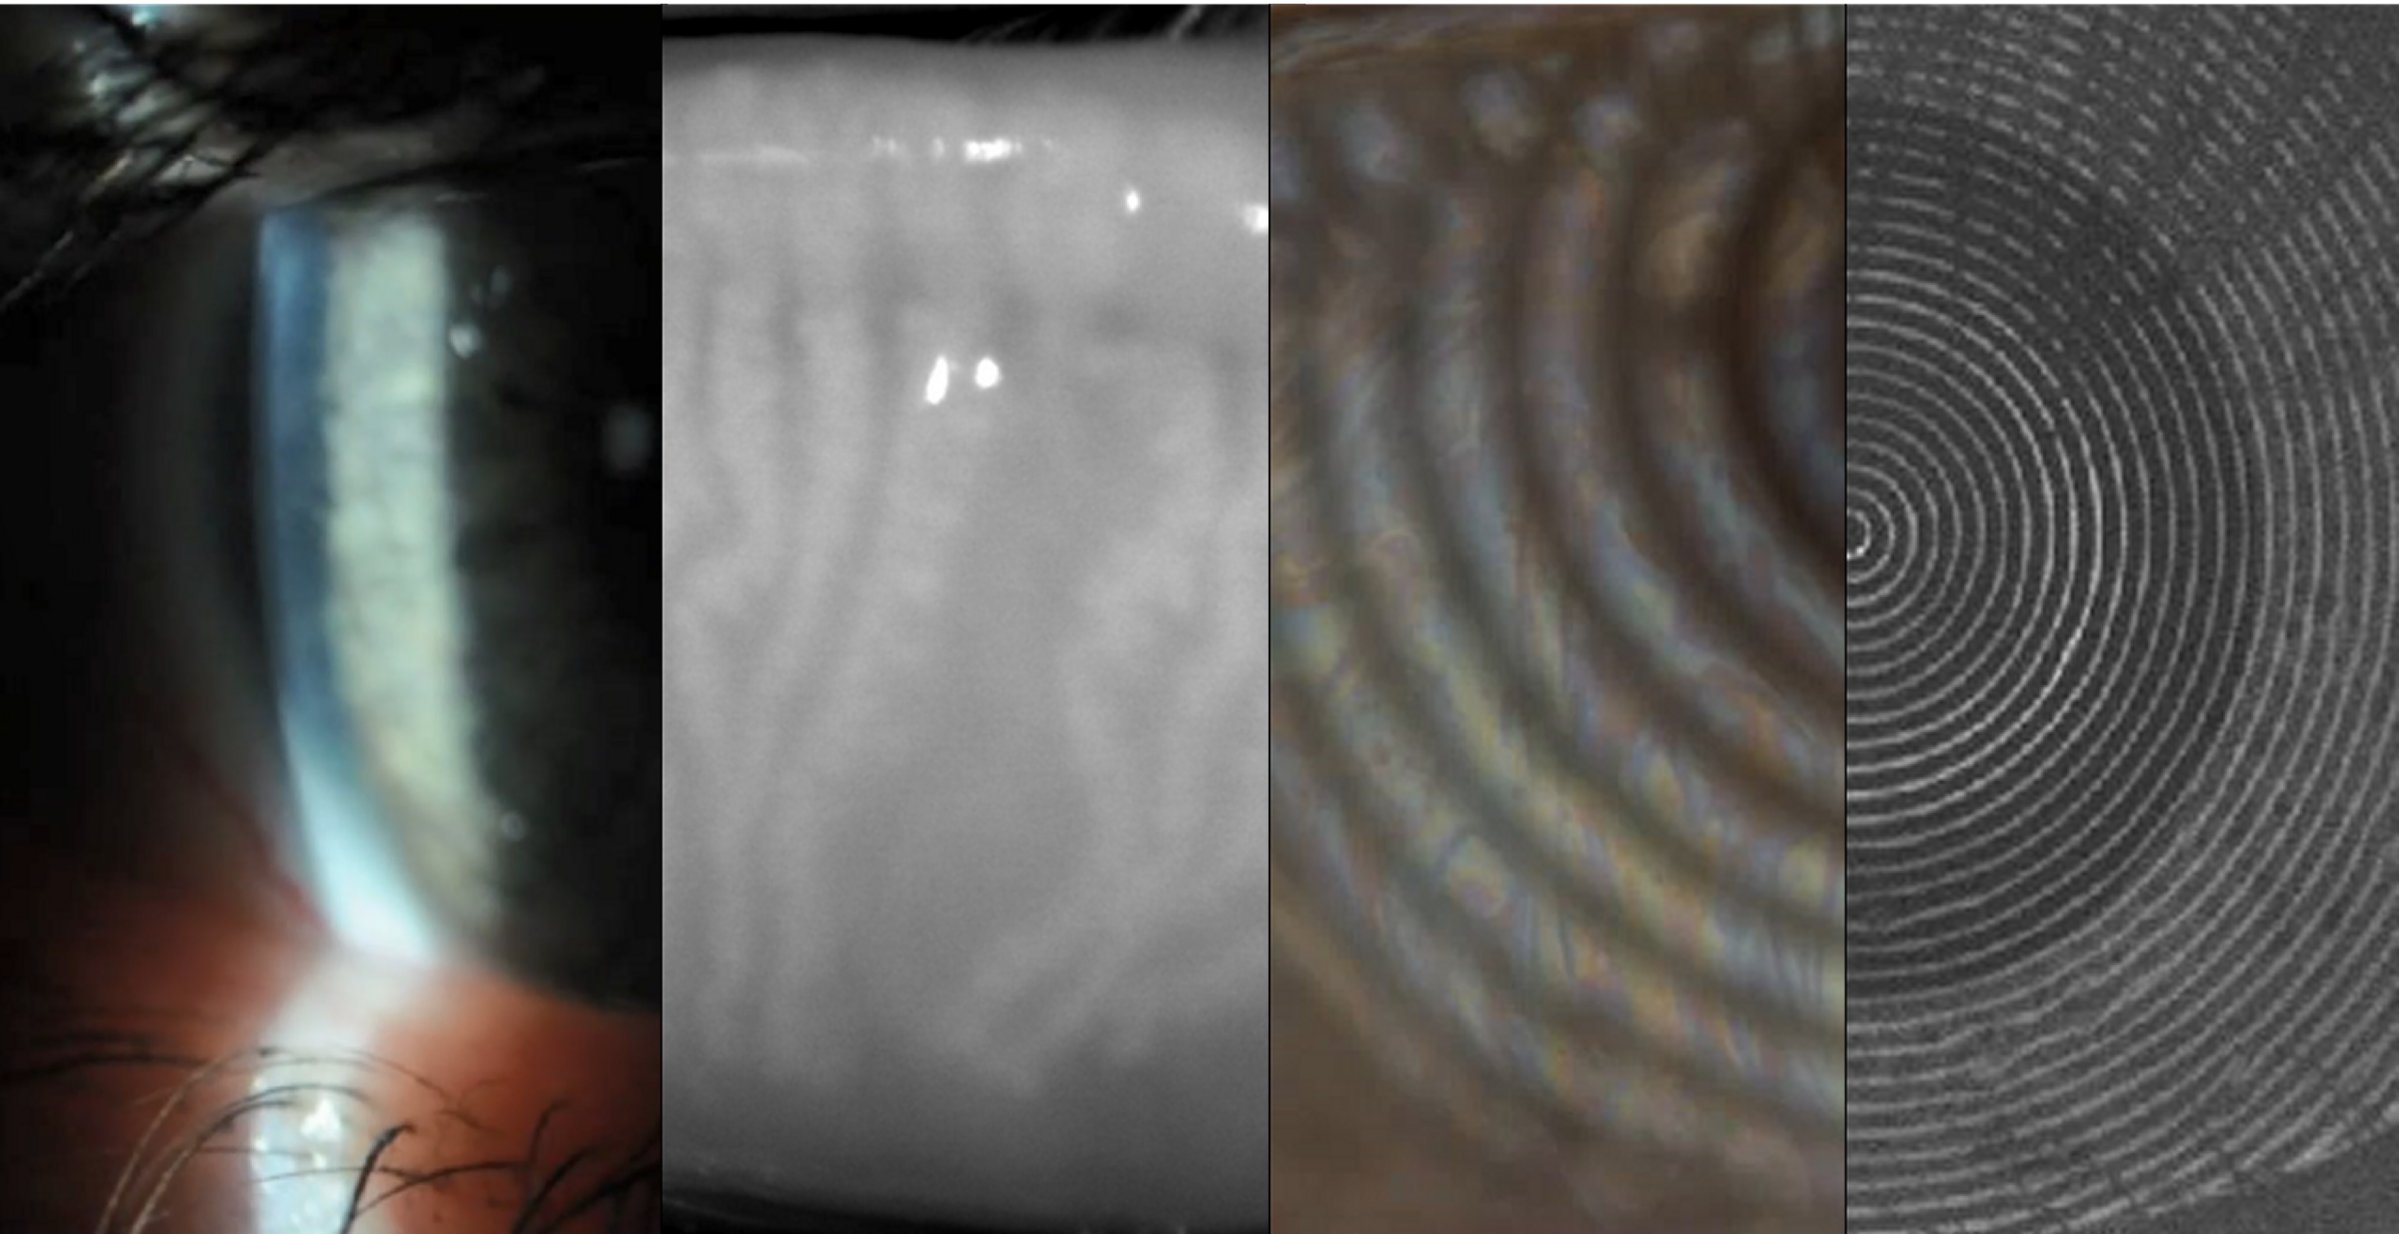

| Stabilizowanie się filmu łzowego po mrugnięciu jest zagadnieniem mało poznanym, a ostatnie doniesienia naukowe wskazują, że ta faza może dostarczyć ważnych informacji o jakości filmu łzowego. Celem projektu jest poznanie fizjologii filmu łzowego zaraz po mrugnięciu, dostarczenie bazowej wiedzy o kinetyce filmu łzowego oraz poznanie zależności pomiędzy fazą stabilizowania się filmu łzowego a jego zachowaniem podczas całego okresu między mrugnięciami. Wykazaliśmy ostatnio, iż za pomocą Interferometru typu lateral shearing (LSI), można wyróżnić aż do pięciu faz kinetyki filmu łzowego (patrz rysunek). Rozwinięcie i udoskonalenie interferometru umożliwi przeprowadzenie dokładnych pomiarów jakości powierzchni filmu łzowego na oku, a zarejestrowane interferogramy będą stanowić podstawę do opracowania metody analizy numerycznej zachowania się filmu łzowego w pierwszej fazie zaraz po mrugnięciu. Celem projektu jest opracowanie kluczowych parametrów, które opiszą w sposób ilościowy kinetykę i biofizyczne własności filmu łzowego, i pomogą w przyszłości znaleźć związki pomiędzy procesem stabilizowania się filmu łzowego po mrugnięciu a chorobami oka związanymi z zaburzoną stabilnością cieczy łzowej. Przy realizacji projektu współpracuję z Robertem Iskanderem z Instytutu Inżynierii Biomedycznej i Pomiarowej Politechniki Wrocławskiej. | ![]() |

| W ostatnich dwóch dekadach operacje refrakcyjne rogówki stały się bardzo popularne. Wiadomo, niestety, iż mogą one powodować zespół suchego oka związany z morfologicznymi i fizjologicznymi zmianami na powierzchni oka i funkcji filmu łzowego. Do pomiaru regularności powierzchni filmu łzowego na oczach po operacji LASIK (laser in situ keratomileusis) i RK (radial keratotomy) użyto interferometr typu lateral shearing. Jasne linie o wysokiej intensywności obserwowane na tle prążków interferencyjnych są interpretowane, jako przełomy w filmie łzowym. Zastosowanie procedur przetwarzania obrazów wykazało powtarzalność kształtu jasnych linii, co sugeruje, że nieregularności na powierzchni filmu łzowego mogą być spowodowane lokalnymi nieregularnościami nabłonka rogówki powstałymi w wyniku operacji refrakcyjnej. |